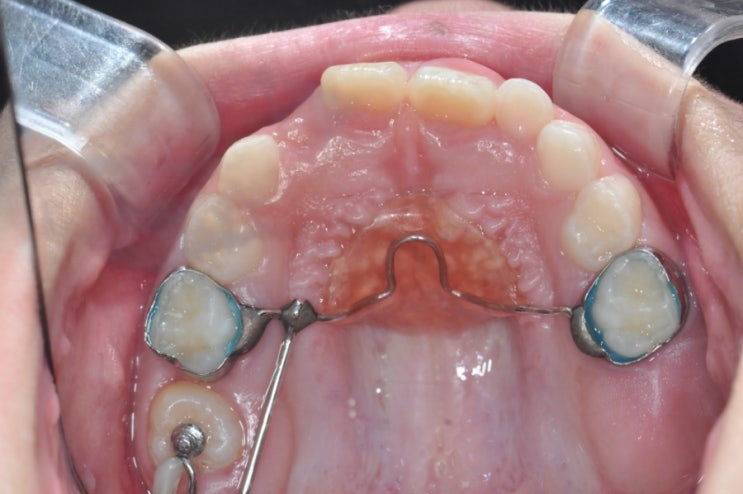

8세 딸 유치를 미는 영구치 어금니 교정 과정 ㅡ 2개월 후 교정기 제거 (총 4개월 걸림)

그래... 드디어 우리 딸의 어금니 교정이 끝이 났다. 8세 때 시작해서 9세 때 끝이 났다. 유치를 미는 영구...